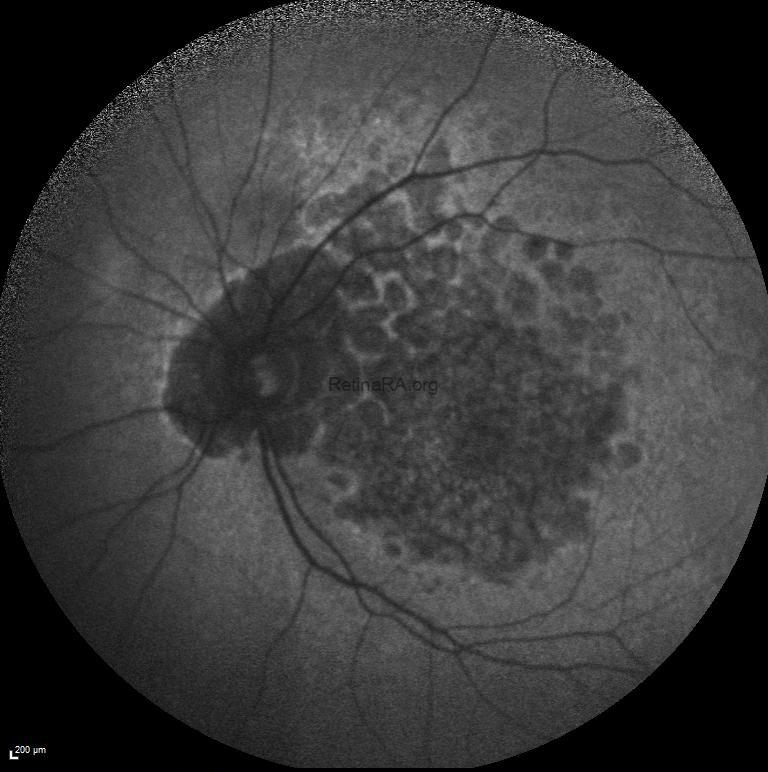

Fundus examination of the right and left eyes revealed subretinal pigment epithelium drusen-like deposits extending from the macula to the mid periphery in both eyes in addition to macular atrophy.

Blue-light macular fundus autofluorescence and wide-field fundus autofluorescence revealed decreased autofluorescence at the macula and increased autofluorescence in mid-peripheral retina.